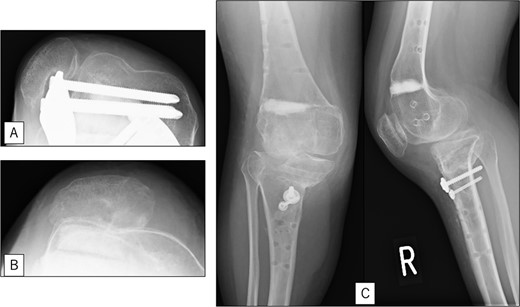

A 23-year-old woman presented with bilateral knee pain and gait abnormalities owing to marked lower extremity deformity. She was diagnosed with EVC as a child but had never been followed up by orthopedics because she was not in pain. On physical examination, marked valgus instability was observed in both knees, and the motion of both knees ranged from 10° to 135°. Radiographic examinations of both knees, including computed tomography, showed valgus deformity, lateral and anterior depression of the proximal lateral tibial plateau, and external rotation deformity of the lower leg. Patellar dislocation was observed in the right knee (Fig. 1). The radiological angles are presented in Table 1. The right knee underwent surgery first, followed by the left 10 months later. Lateral and medial skin incisions were made. Extensive lateral retinacular release, fractional lengthening of the distal lateral hamstring, and Z-lengthening of the iliotibial band were then performed. At this stage, peroneal nerve strain was identified, and decompression of the peroneal nerve was performed. Osteotomy was subsequently performed on the tibia. Closed-wedge varus and derotational osteotomy of the proximal tibia and open-wedge varus osteotomy of the distal femoral varus were performed. In addition, vastus medialis advancement was performed on the right knee, and patellar realignment was achieved in extension (Fig. 2). However, the knee showed a subluxation tendency owing to flexion of >30°; therefore, the postoperative rehabilitation plan progressed more slowly than that of the left knee. Range of motion training began on the left knee immediately after surgery without any restrictions, but on the right knee only after 3 weeks of postoperative immobilization in the extended position. However, ambulation exercise was performed on both knees with no loading for 3 weeks, then partial loading was initiated, and full loading was permitted at 8 weeks postoperatively. Early postoperative standing radiography showed residual mild valgus deformity of the lower limbs (Fig. 2, Table 2). In addition, the right knee showed patellar re-dislocation 2 months postoperatively, and the patellar deformity gradually progressed owing to the femoral implant; therefore, the patient underwent implant removal, tibial tubercle transfer, and medial patellofemoral ligament reconstruction 1.5 years after the initial surgery (Fig. 3). Six months later, she fell while walking and developed a fracture at the osteotomy of the right femur; open reduction and internal fixation were performed (Fig. 4). The remaining years passed uneventfully, and 10 years after the initial surgery, the patient still had mild valgus deformity of the lower limbs, but had no recurrence other than that experienced immediately after surgery, no complaints of knee pain, and a stable gait (Fig. 5, Table 2).

Radiography after fracture at the osteotomy of the right femur. (A) anteroposterior and lateral view immediately after fracture. (B) After open reduction and internal fixation.